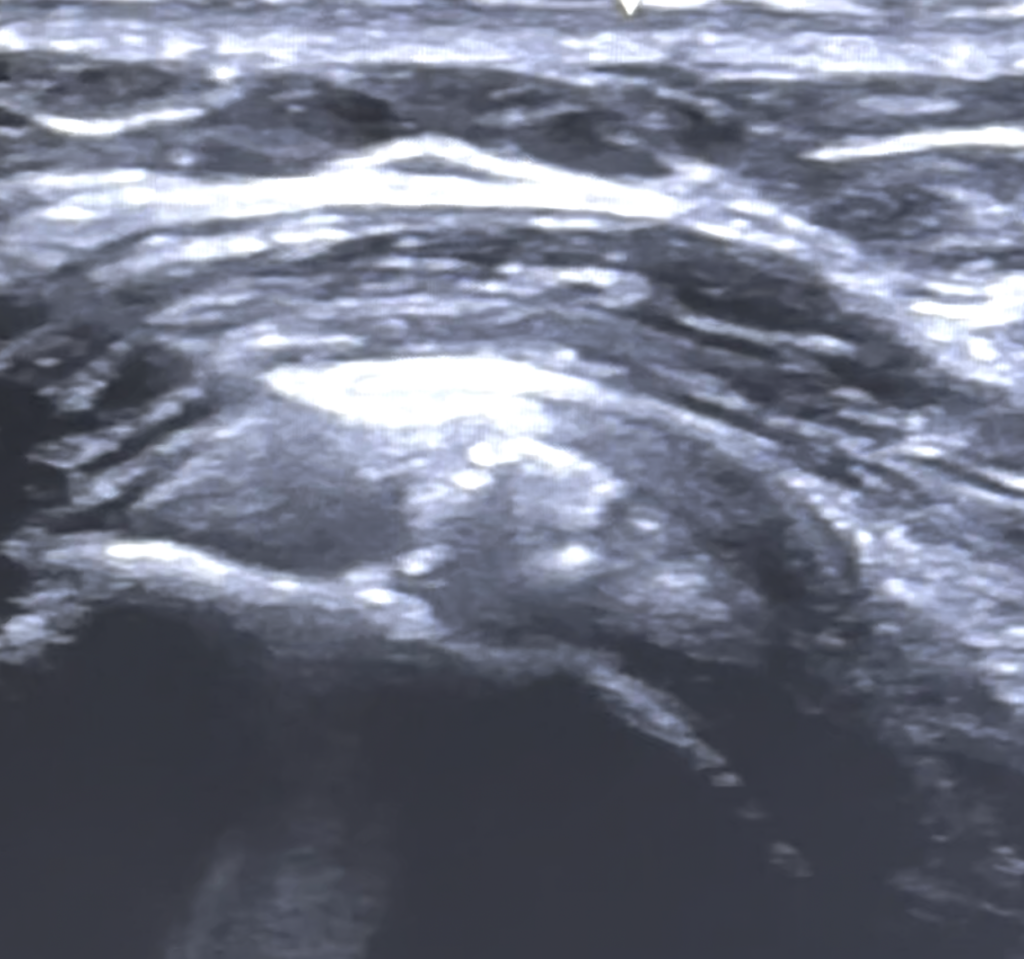

La ecografía es una técnica diagnóstica que tradicionalmente se ha empleado para realizar el diagnóstico mediante ultrasonidos de lesiones de partes blandas en el aparato músculo-esquelético (tendinopatías, lesiones musculares, entensopatías, lesiones meniscales, quistes, etc)

Actualmente se ha ampliado sus indicaciones para hacer tratamientos ecoguiados o ecoasisitidos para inyectar sustancias farmacológicas (anestésico, corticoides) o regenerativas (plasma rico en plaquetas, concentrado de médula ósea). O también para hacer procedimientos terapéuticos sencillos como eco-lavado de calcificaciones, evacuación de quistes sinoviales, neurolisis, tenolisis y un amplio abanico de posibilidades que podemos realizar los traumatológos y médicos deportivos.